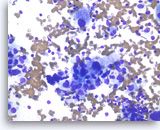

Ductal adenocarcinoma #2,

Pancreas FNA, Direct Smear.

The aspirates show single and clusters of malignant epithelial cells with unpredictable nuclear to cytoplasmic ratios. Metachromatic extracellular mucinous material is readily seen in the background as well as intermixed with epithelial cell clusters.

10X

Ductal adenocarcinoma #2,

Pancreas FNA, Direct Smear.

The aspirates show single and clusters of malignant epithelial cells with unpredictable nuclear to cytoplasmic ratios. Metachromatic extracellular mucinous material is readily seen in the background as well as intermixed with epithelial cell clusters.

10X